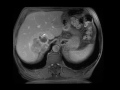

Retroperitoneal Liposarcoma

Multiple MR images demonstrate a large mass arising in the right aspect of the retroperitoneum, in roughly the vicinity of the IVC and right adrenal gland. This was found to be a retroperitoneal liposarcoma.